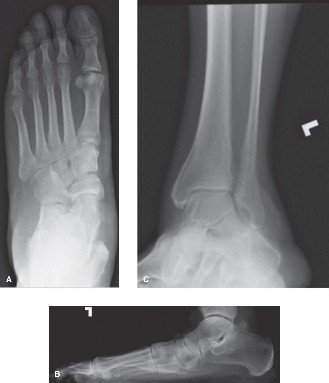

A 52-year-old male presents to your office reporting increased medial and lateral hindfoot pain for the past …